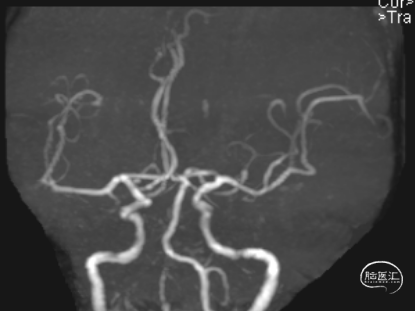

头颈CTA:左侧椎动脉起始、左侧锁骨下动脉重度狭窄。

LSub

LV1

症状性左锁骨下重度狭窄;症状性左椎动脉重度狭窄。

术后头晕呕吐,当日DWI:左侧小脑梗死,MRA未见明显大血管栓塞。

术后第3天患者恶心、呕吐症状消失,仍有头晕,复查DWI及MRA。